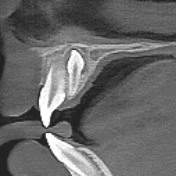

前歯クラック

(亀裂) -

70μm(Voxel Size)高精細モード搭載

End、根尖、破析、分岐部病変など精細読影をサポートします。

CT撮影時、Free FOVで撮影に必要な領域を絞り込み、

的確に高解像度70μmの世界トップレベルのCT画像を再現します。-